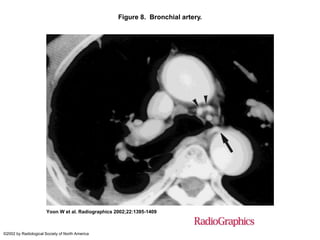

Figure 8. Bronchial artery.

Yoon W et al. Radiographics 2002;22:1395-1409

©2002 by Radiological Society of North America

Figure 8. Bronchialartery. Yoon W et al. Radiographics 2002;22:1395-1409 ©2002 by Radiological Society of North America

• #30 Figure 8.  Bronchial artery. Contrast-enhanced CT scan shows a pathologic right bronchial artery (arrow) that originates from the anteromedial aspect of the thoracic aorta and a hypertrophic left bronchial artery in the aortopulmonary window (arrowheads).